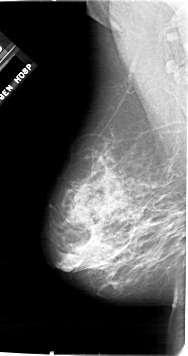

A_1771_1.LEFT_MLO

LEFT_MLO LINES 6751 PIXELS_PER_LINE 3556 BITS_PER_PIXEL 12 RESOLUTION 43.5 NON_OVERLAY